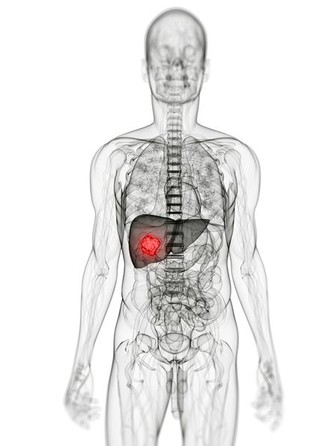

③疾病需要:指一些疾病導致的維生素缺乏,如肝功能不全患者容易出現維生素K合成障礙。